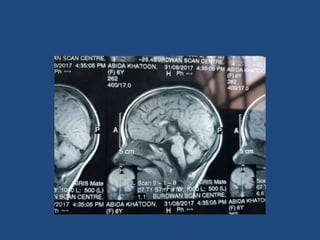

• History of trauma, brain tumor, cranial

irradiation or organic or congenital

abnormalities of hypothalamic – pituitary

abnormalities (MRI)

• If MRI of HPT is abnormal then GH provocation

test is optional

• Pituitary abnormalitity- hypoplasia, ectopic

posterior pituitary, abnormal stalk

• Severe short stature (Height<-3SD) with